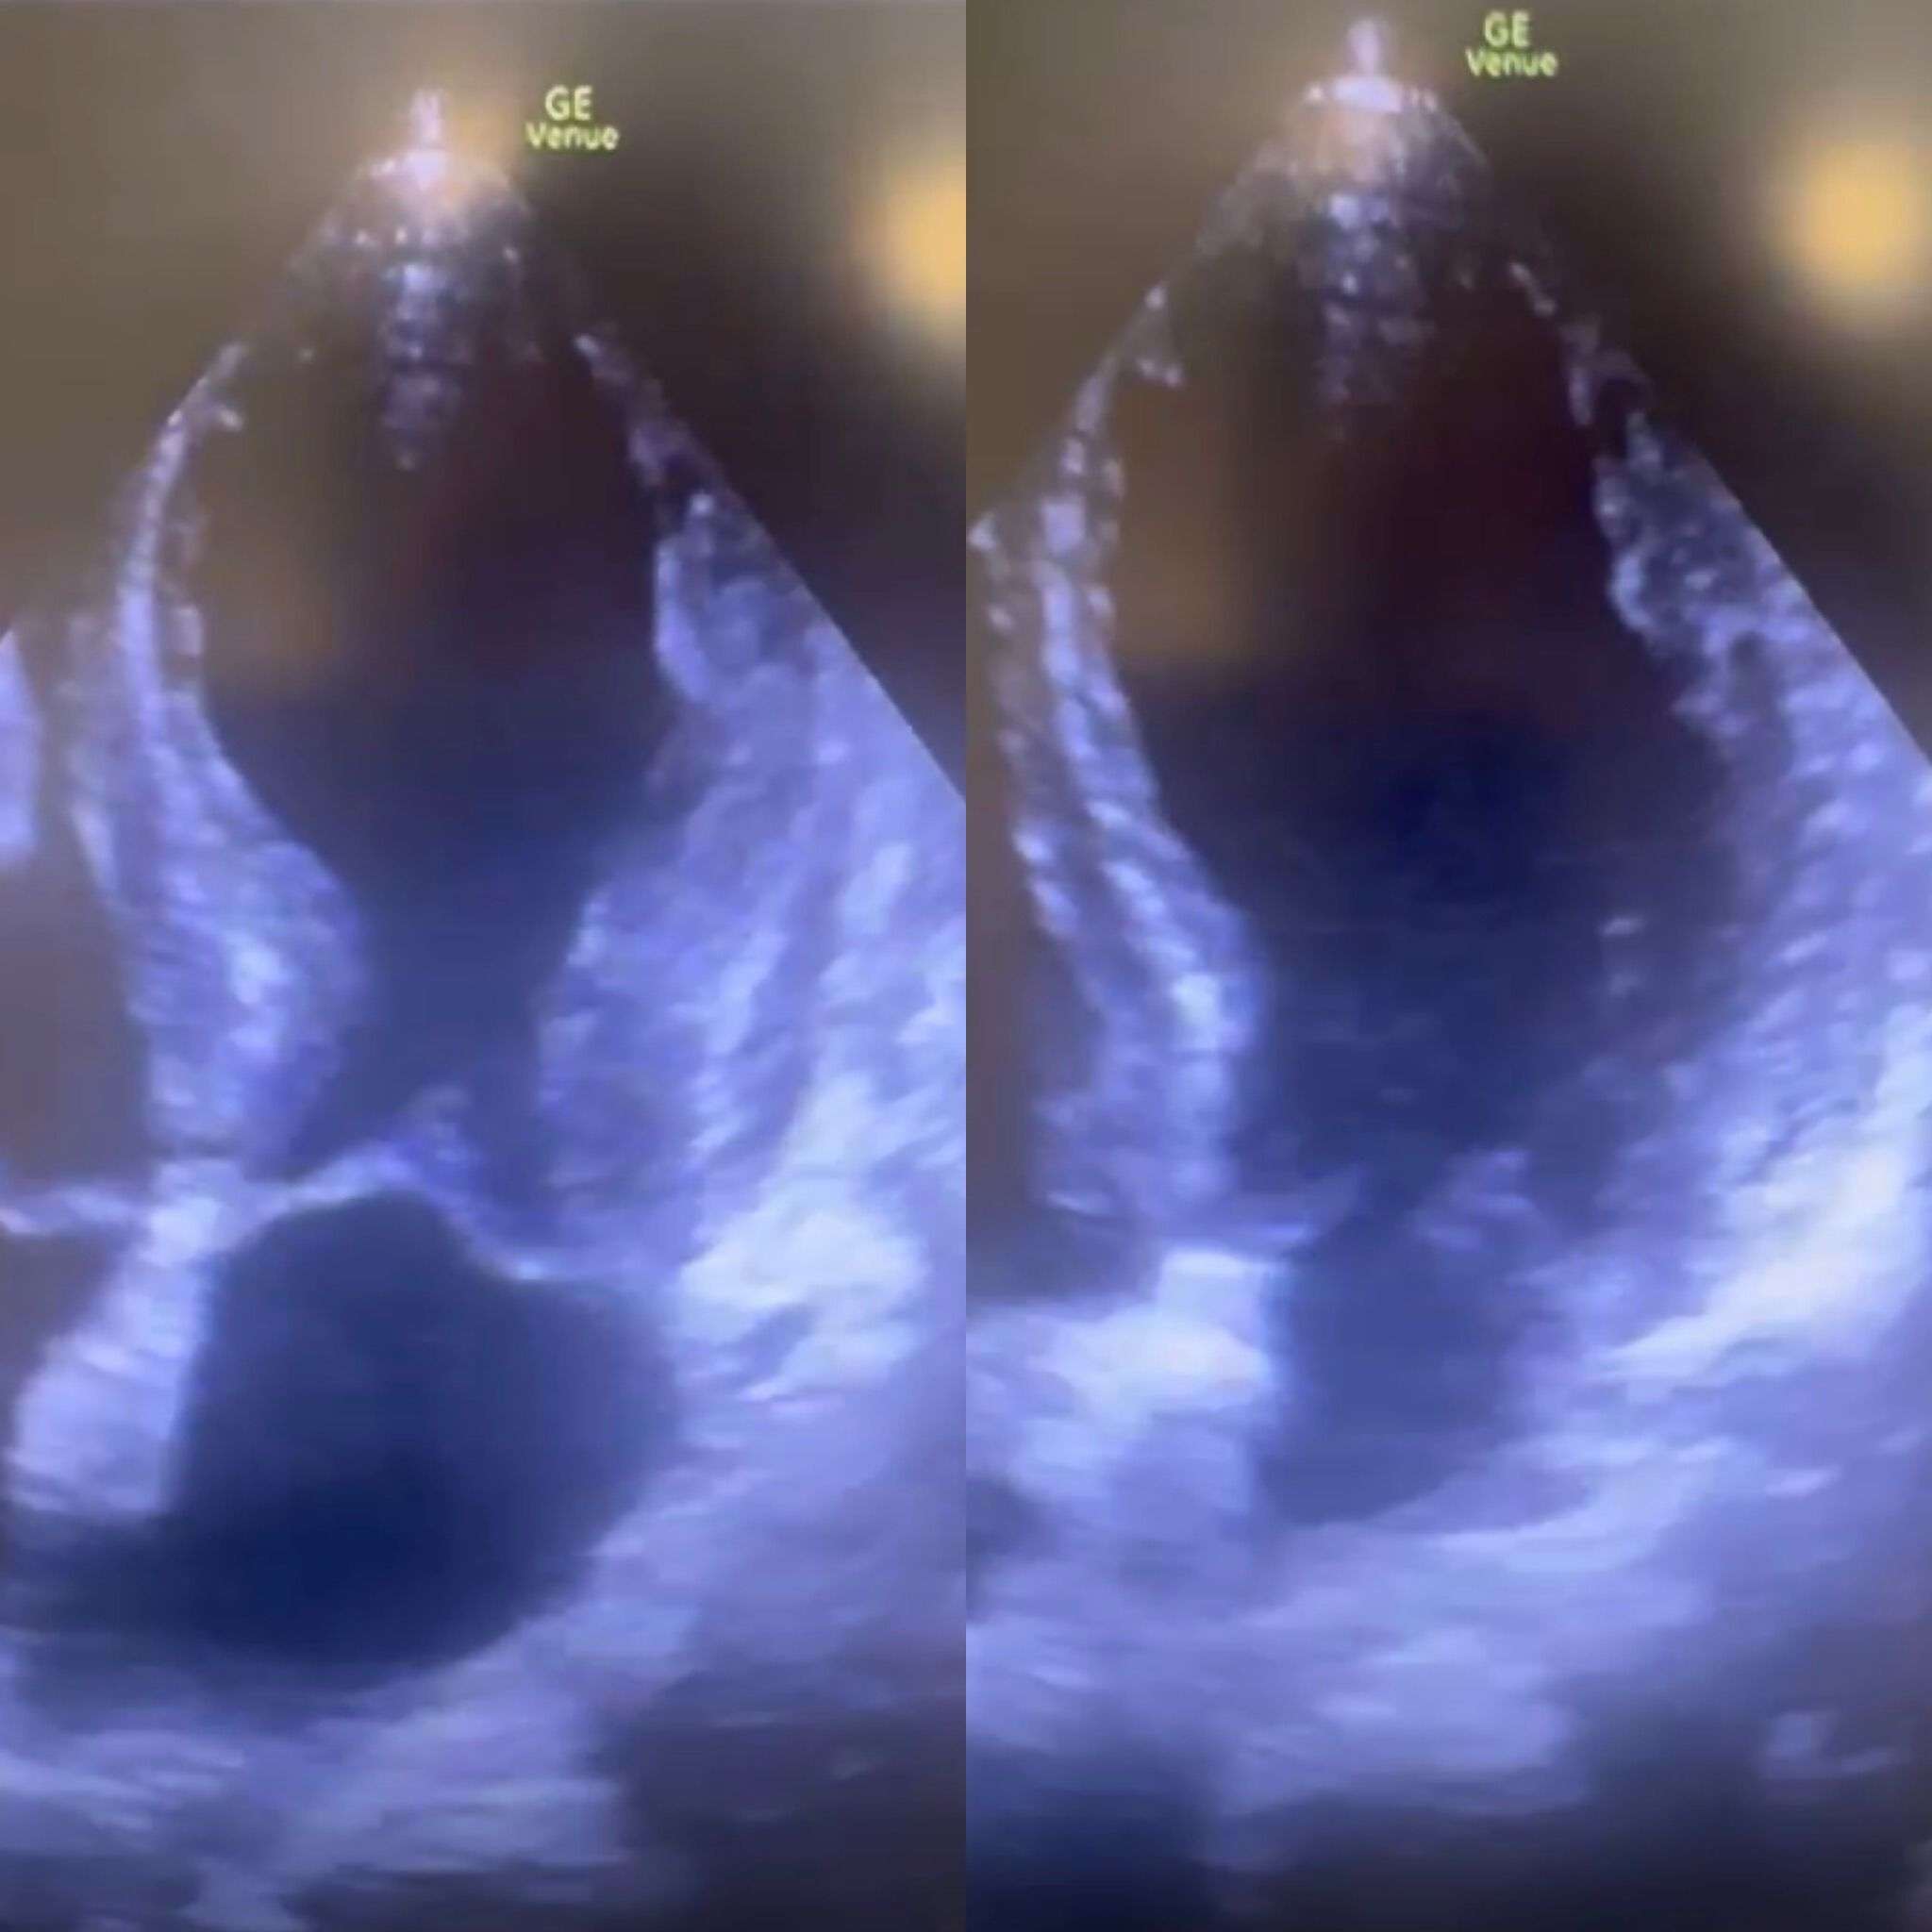

כך נראה לב שבור:

בתמונה מימין, רואים את הלב במצב הרפוי (דיאסטולה).

בתמונה משמאל, רואים את הלב במצב מכווץ (סיסטולה), כשרק הבסיס שלו מתכווץ והחוד נשאר רפוי ומקבל מראה של בלון, ולא מתכווץ גם הוא, ולכן זה נקרא apical ballooning.

לב תקין מול לב שבור. צילום: דוברות כללית